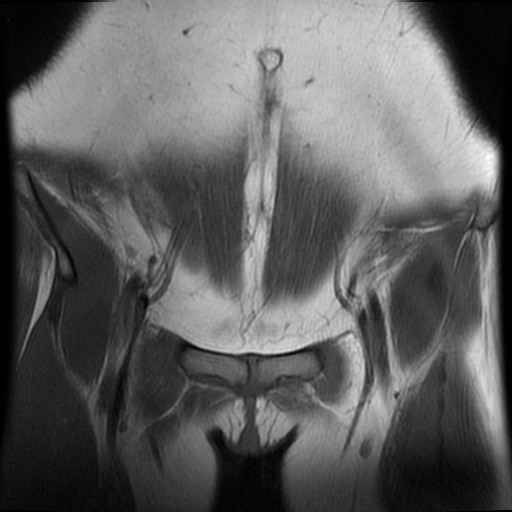

Bekken